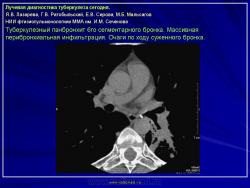

Лучевая диагностика туберкулеза сегодня

Я.В. Лазарева, Г.В. Ратобыльский, Е.В. Серова, М.Б. Мальсагов

НИИ фтизиопульмонологиии ММА им. И.М. Сеченова